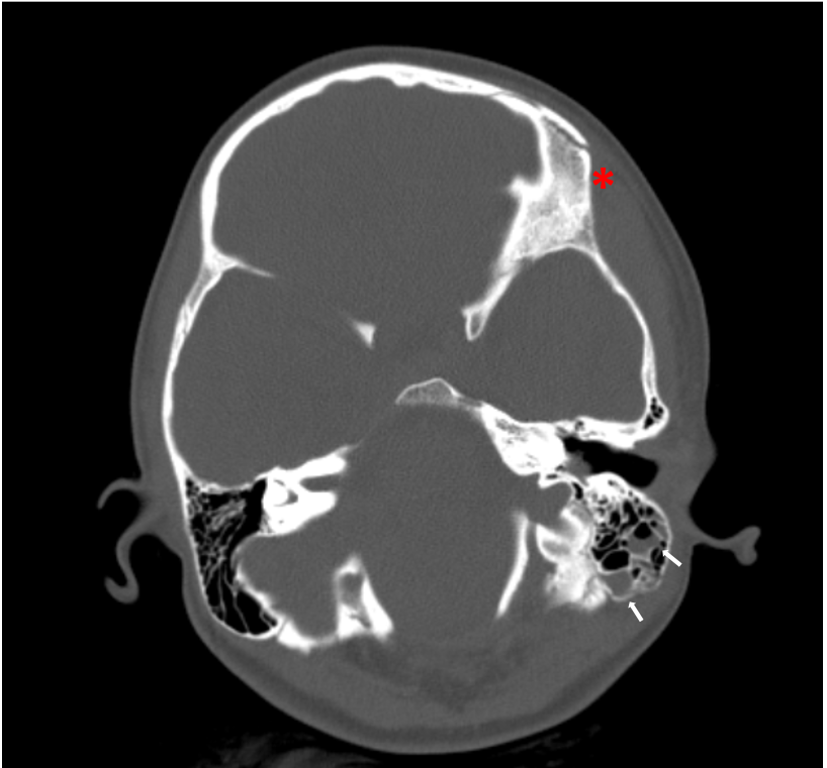

Si decide quindi di eseguire una TC del capo, che evidenzia la presenza di un ematoma subdurale frontale e di una frattura dell’osso temporale (Figura 2). La paziente viene trasferita in Neurochirurgia per la prosecuzione delle cure. Viene quindi dimessa dopo 48 ore di osservazione, con una TC di controllo stabile, un audiogramma nella norma e l’indicazione ad assumere amoxicillina-acido clavulanico per 10 giorni.